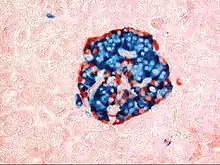

A pancreatic islet, stained.

A pancreatic islet, stained. A pancreatic islet, showing alpha cells

A pancreatic islet, showing alpha cells A pancreatic islet, showing beta cells.

A pancreatic islet, showing beta cells.